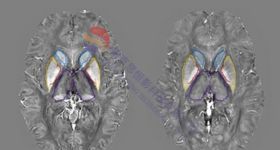

思影科技将于11月--2025年11日)在南京举办第七十届磁共振脑网络数据处理班(详见课表安排)。 DTI脑网络构建分...

思影科技将于11月-- 2025年2日—下周二1、培训简介 作为磁共振成像技术的一项重大突破,扩散成像是目前唯一...